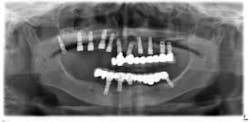

An 81-year-old female with stent placement 10 years ago taking no medications presented with a chief complaint that her old prosthesis broke, and she cannot chew and function. She had a previous bridge consisting of an implant in the No. 1 site combined with the natural teeth and implants in the 8, 9, 14, 15. No. 8, 9 implants were malpositioned with a 35-degree angle and significant mucogingival defects.

Various treatment options were explained to the patient, and a treatment plan consisting of Coldwell-Luc external sinus lift with bilateral block placement in area 5 to 7 and 10 to 12 was agreed upon.

Under local anesthesia, a full thickness flap was elevated from the upper right to upper left posterior segments. Using a piezoelectric handpiece, a buccal window hinge osteotomy was elevated in the maxillary right posterior region. A mixture of DFDBA, anorganic bovine bone, and PRF was placed. A collagen membrane was used to cover the buccal window. Simultaneously, two puros J-block allografts were secured in the 5 to 7 and 10 to 12 region with stainless steel screws (1.6 x 8 mm screws). A mixture of DFDBA, anorganic bovine bone and PRF was placed over each area and covered with PRF sheet and a collagen membrane. Primary closure was obtained with CV-5 Goretex sutures. Healing was uneventful. After six months of healing, six straight implants were placed in sites 3, 4, 5, 6, 11, and 12. Healing abutments were placed at stage I. Healing was uneventful. After four months of healing, six custom abutments were fabricated by his dentist and cover screws were placed on implants 8 and 9 and converted into pontics.

Removing the implants would have created a large buccal defect, which would have created elongated pontics in the maxillary anterior region. The prosthesis was completed, and the patient is stable and highly appreciative of her ability to smile and chew.

Case 2: Sinus lift, bone graft, PRP, and after healing implant placement